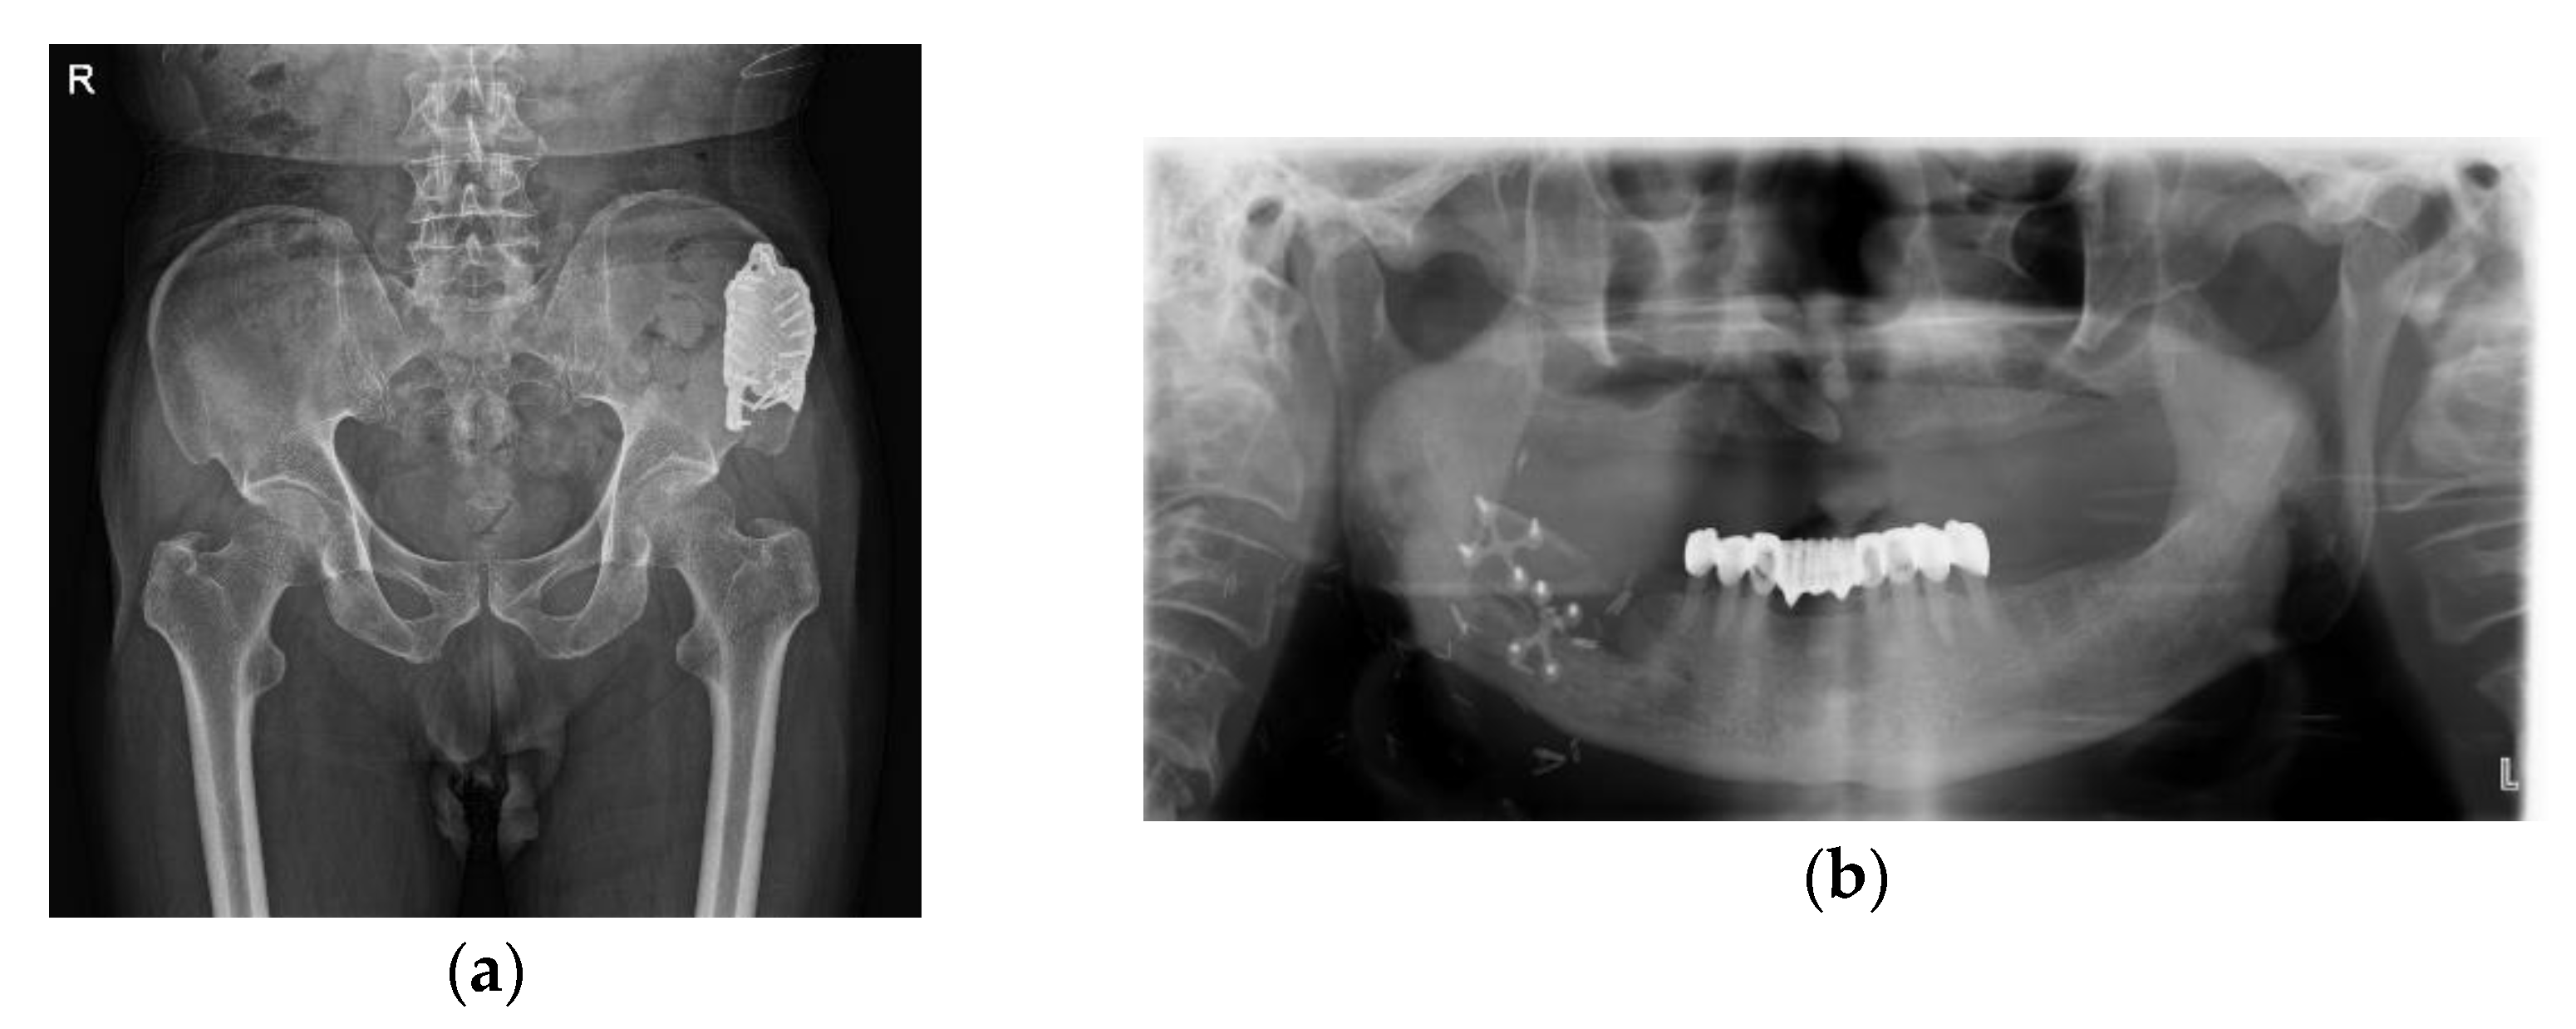

From 1 month postoperatively, the patient was able to stand and walk and was able to live without any discomfort for up to 1 year postoperatively. There was no recurrence of the ameloblastoma and no other complications were observed, so implants were placed 1 year after the operation (Figure 9).

Figure 9.

Postoperative radiograph after 1 year: (a) patient-specific implant shown on right iliac bone after 1 year; (b) well-reconstructed mandible and implants were installed 1 year after the operation.

2.3. Case 3: Verrucous Carcinoma on Right Upper Gingiva

A 78-year-old female presented at the department of oral and maxillofacial surgery with a growing mass on the right upper gingiva (Figure 10).

Figure 10.

Initial examinations: (a) intraoral photograph showed the proliferative lesion with indistinct borders on the right upper gingiva; (b) panoramic view.

An incisional biopsy diagnosed a verrucous carcinoma. CT and PET-CT were taken. A palatal lesion with intense fluorodeoxyglucose (FDG) uptake was observed on the radiological images. Therefore, a partial maxillectomy and DCIA flap reconstruction were planned.

A monocortical DCIA flap was harvested with internal oblique muscle. Micro-anastomosis was performed on the right facial artery and vein. Harvested iliac bone was fixed with a miniplate and screws.

The patient complained of pain in the donor site on the 16th postoperative day when moving out of bed. A fracture line on the iliac donor site was seen on the radiograph of the iliac bone (Figure 11).

Figure 11.

Radiograph of left ilium; fracture line on iliac donor site was seen.